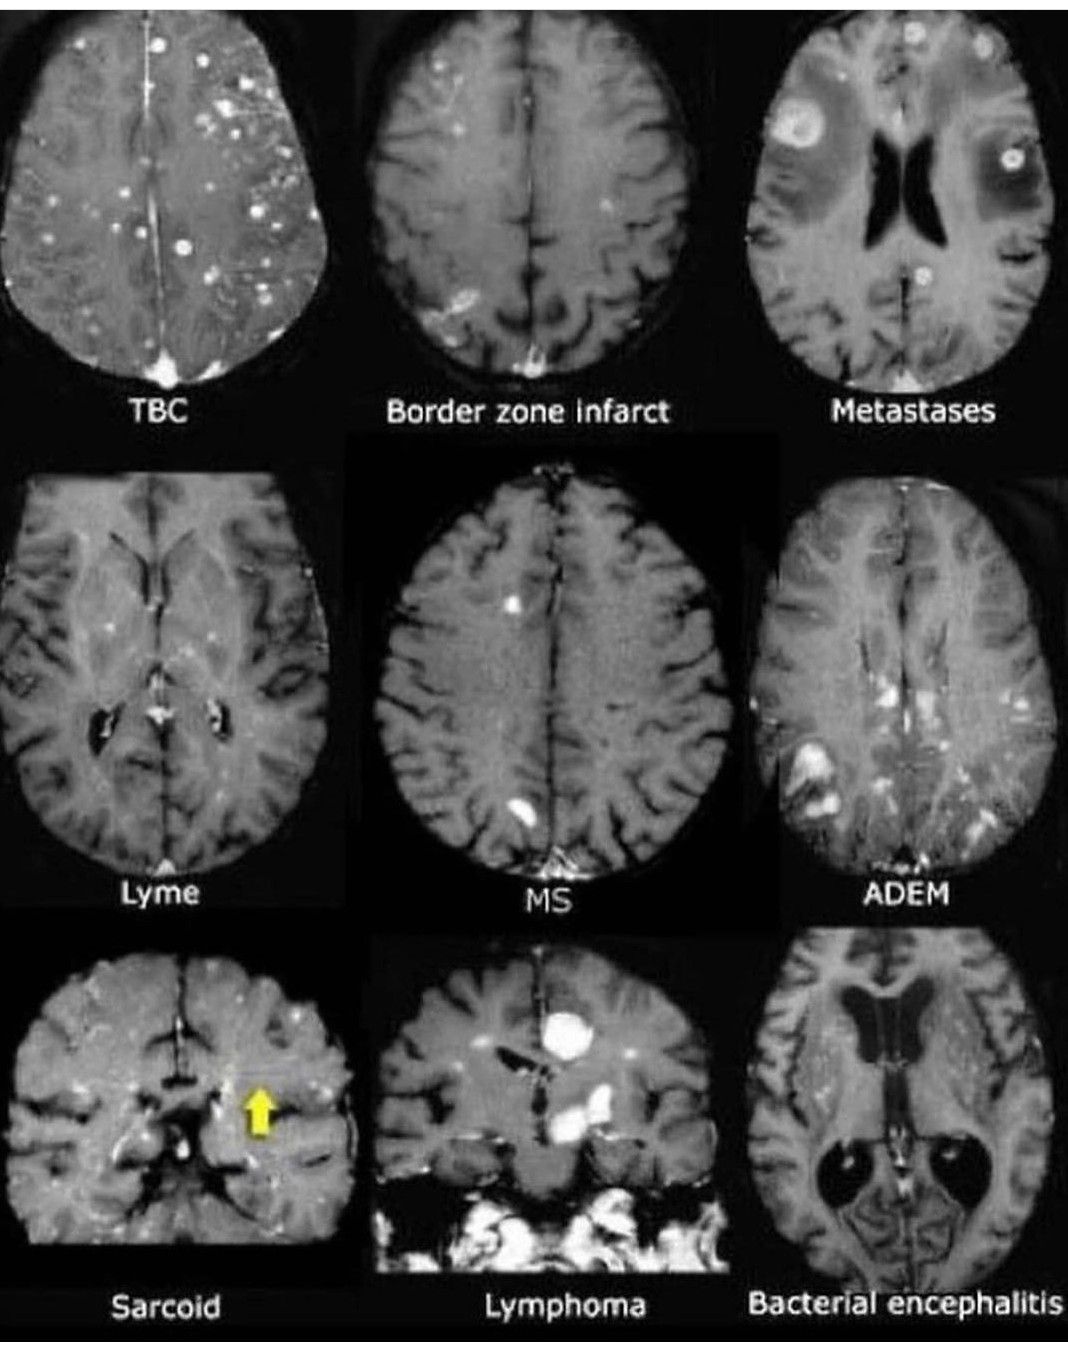

CT Scan of Brain

CT Brain showing different pathologies.